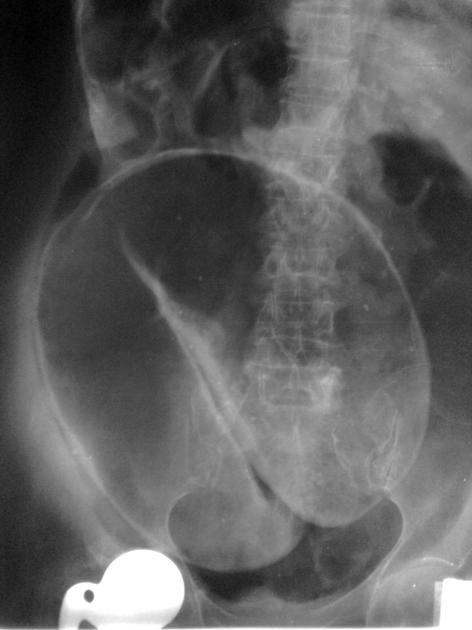

Petit papi avec un gros ventre, arrêt des matières et des gaz depuis 24h. Il a bien mal comme il faut. Vous lui faites un ASP alors que ce n’est plus dans les reco HAS: qu’est ce que c’est?

Volvulus du sigmoïde